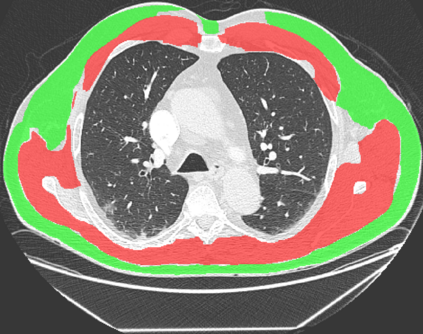

The COVID-19 pandemic has had a considerable impact on day-to-day life. Tackling the disease by providing the necessary resources to the affected is of paramount importance. However, estimation of the required resources is not a trivial task given the number of factors which determine the requirement. This issue can be addressed by predicting the probability that an infected patient requires Intensive Care Unit (ICU) support and the importance of each of the factors that influence it. Moreover, to assist the doctors in determining the patients at high risk of fatality, the probability of death is also calculated. For determining both the patient outcomes (ICU admission and death), a novel methodology is proposed by combining multi-modal features, extracted from Computed Tomography (CT) scans and Electronic Health Record (EHR) data. Deep learning models are leveraged to extract quantitative features from CT scans. These features combined with those directly read from the EHR database are fed into machine learning models to eventually output the probabilities of patient outcomes. This work demonstrates both the ability to apply a broad set of deep learning methods for general quantification of Chest CT scans and the ability to link these quantitative metrics to patient outcomes. The effectiveness of the proposed method is shown by testing it on an internally curated dataset, achieving a mean area under Receiver operating characteristic curve (AUC) of 0.77 on ICU admission prediction and a mean AUC of 0.73 on death prediction using the best performing classifiers.